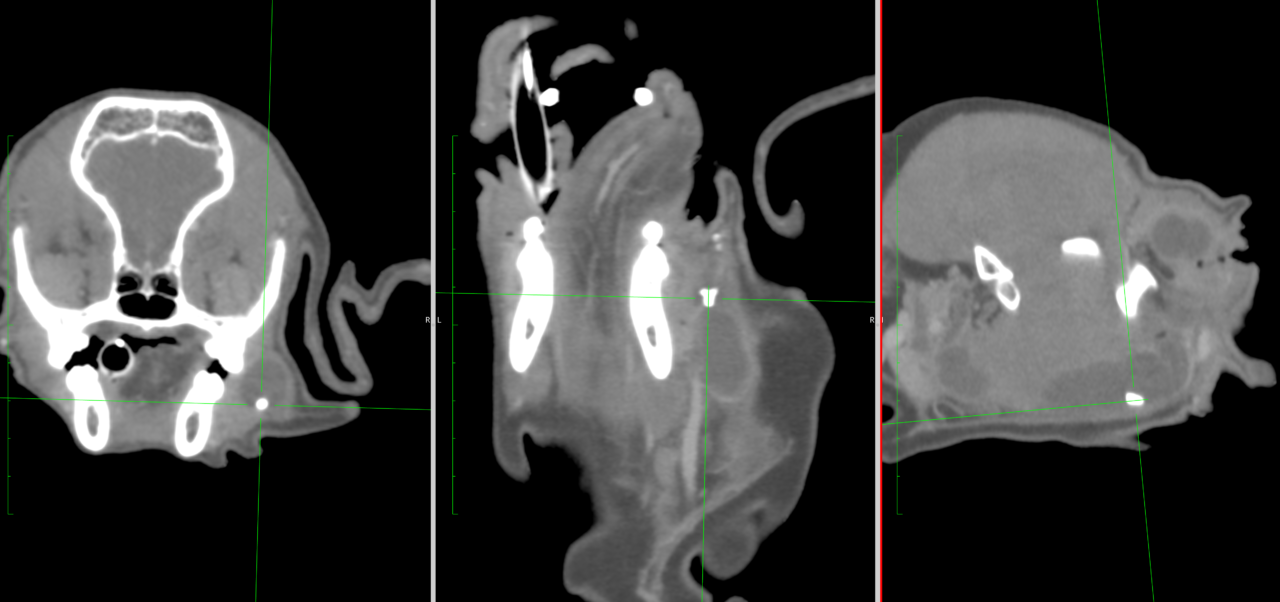

犬の顔面が腫れてきたので、精密検査と必要に応じて手術をしてほしい。主治医からのリクエスト。CT検査と細胞診では唾液腺嚢胞と唾石の形成が疑われた。外科切除の後、この嚢胞の病理検査を行うと、耳下腺領域の嚢胞状腫瘤(6×3×1.5㎝)および右下顎腺(3×2.5×1.3㎝)に嚢胞形成が認められた。嚢胞壁の細胞は唾液腺導管に類似した形態を示し、炎症細胞浸潤や出血が確認された。リンパ節には液体の貯留による嚢胞状変化が観察されるが、構造は保たれている。明らかな腫瘍性の細胞は確認されていない。下顎腺において唾液腺導管の拡張が顕著であった。